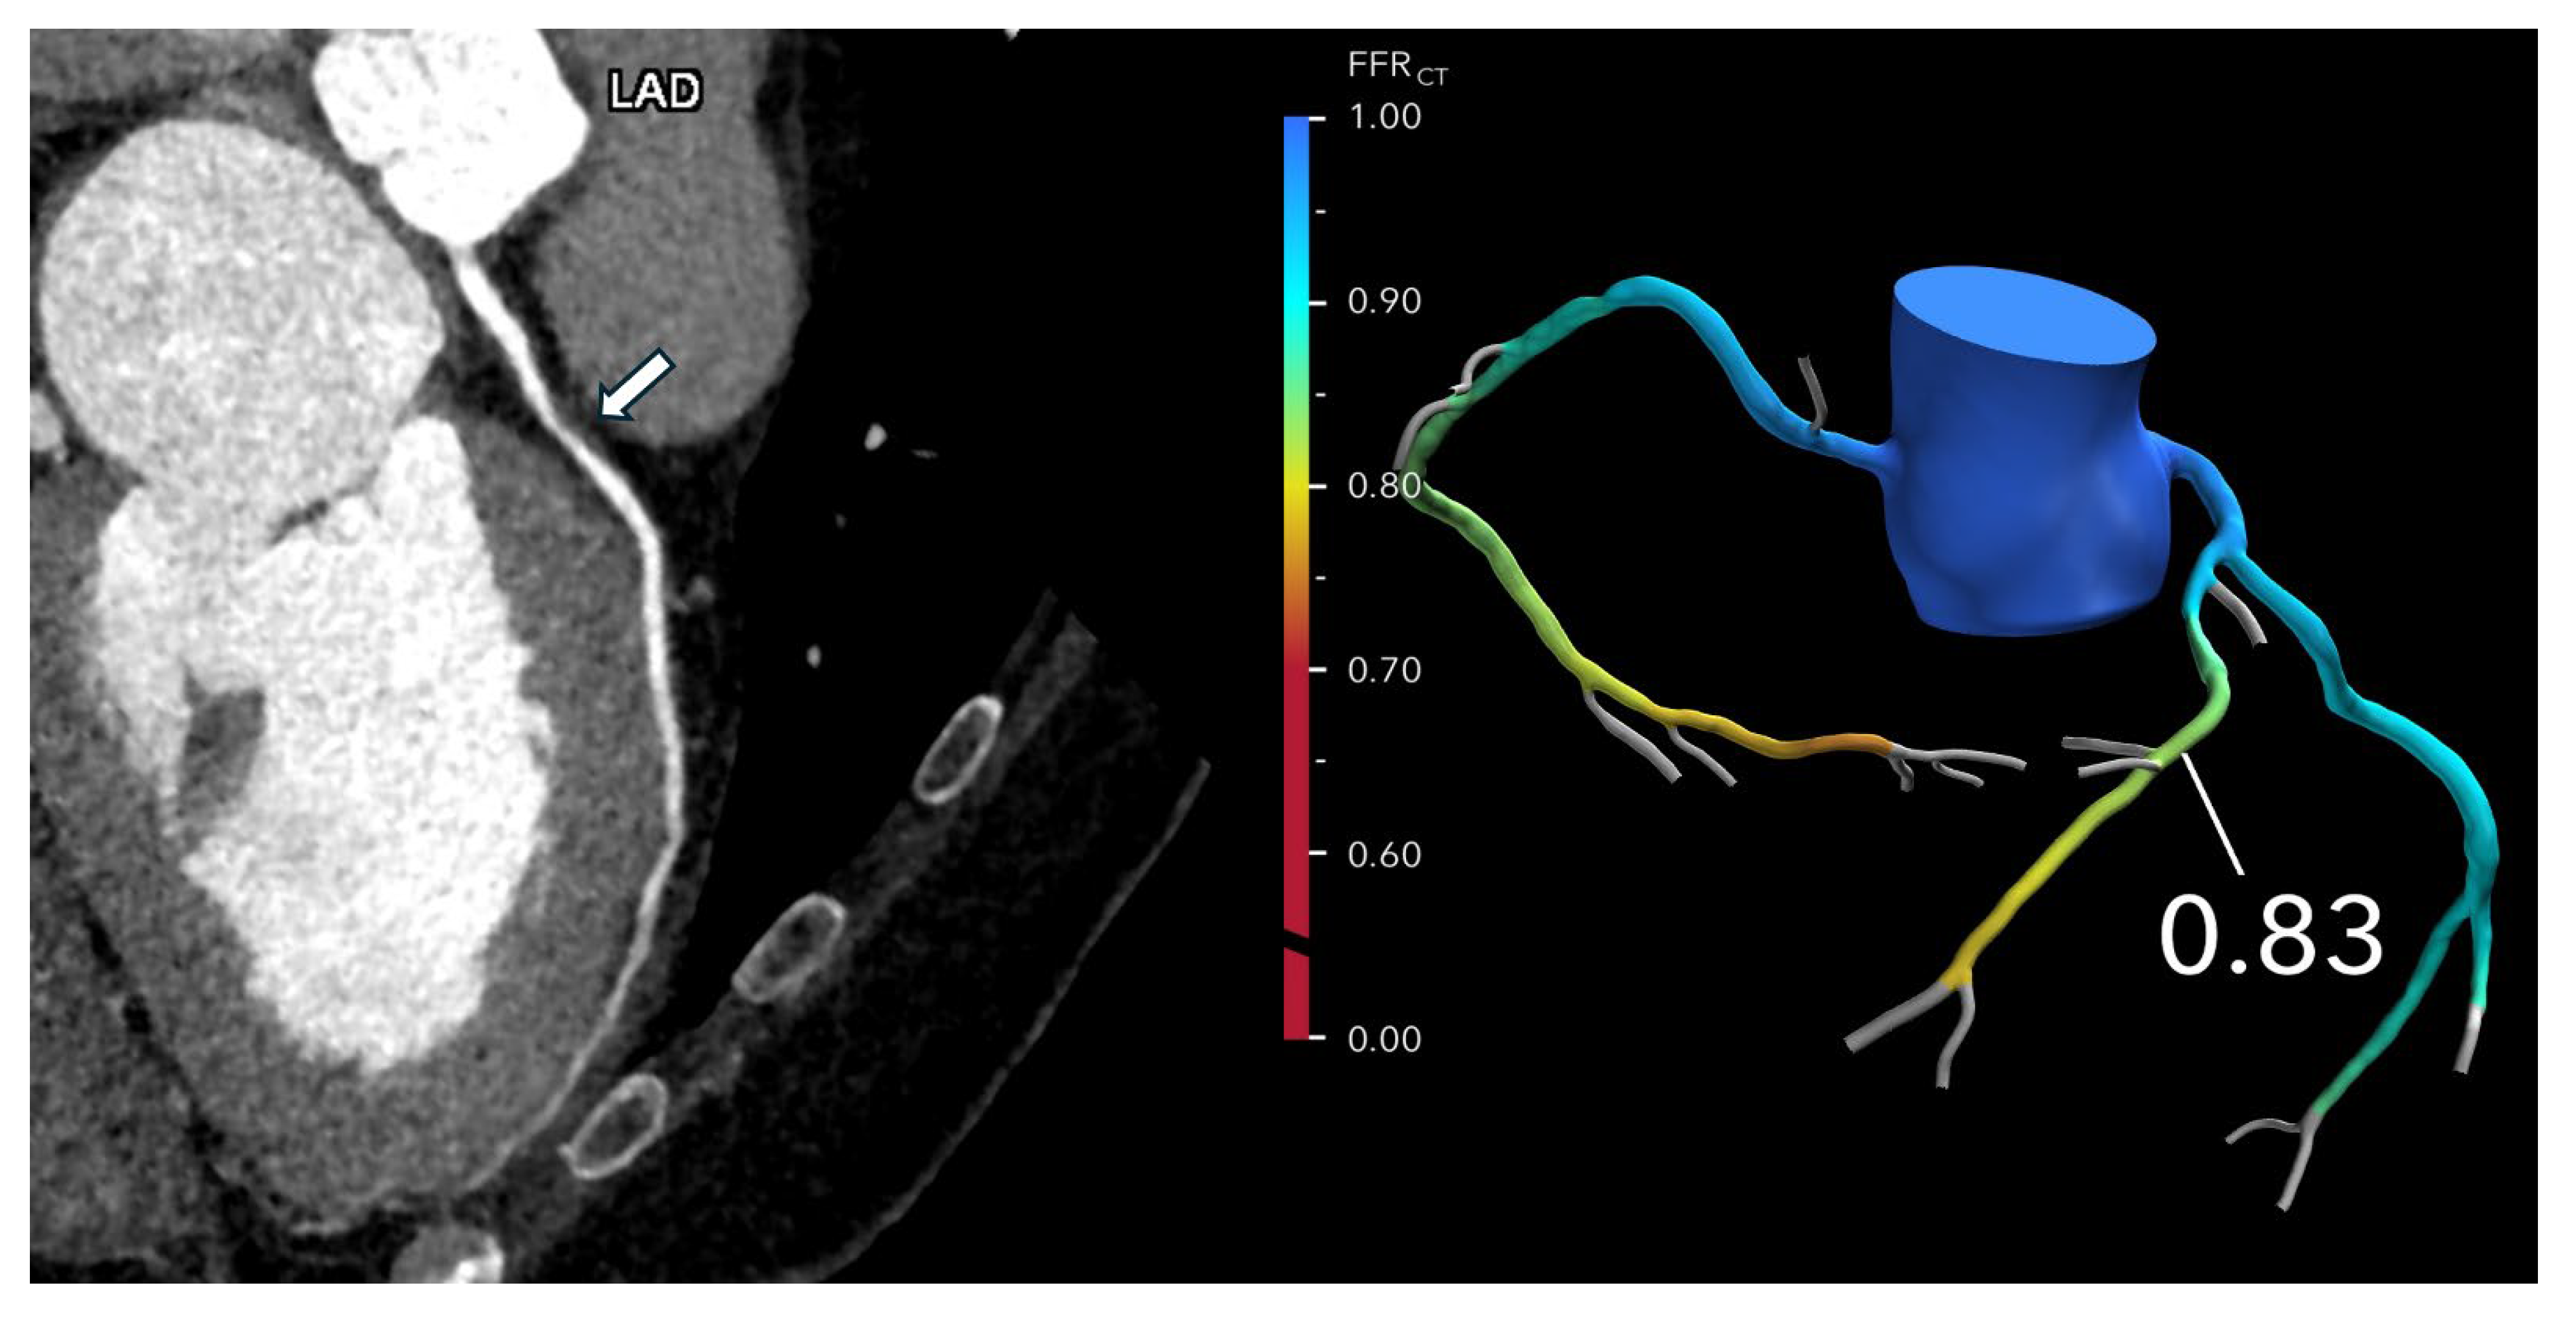

7. When and How to Use FFR-CT: Guidance for Coronary CTA Interpretation and Reporting

FFR-CT is particularly valuable in evaluating patients with intermediate-risk coronary anatomy, typically characterized by one or more lesions causing 30–69% stenosis, or ≥70% stenosis in vessels other than the left main or proximal left anterior descending (LAD) artery. In these cases, FFR-CT helps determine the need for ICA versus optimal medical therapy (OMT). If the FFR-CT is >0.80, the likelihood of hemodynamically significant CAD is low, and patients can generally be managed safely with OMT alone, potentially avoiding unnecessary ICA or revascularization (Figure 2 and Figure 3).

Figure 2. Optimizing treatment decisions with FFR-CT: (Left): A curved MPR coronary CTA image of the LAD in a 62-year-old man with atypical chest pain reveals severe stenosis (>70% diameter reduction) in the proximal LAD (arrow). (Right): The FFR-CT image demonstrates a value of 0.83 measured 2 cm distal to the lesion, indicating normal flow. As a result, invasive coronary angiography was deferred, and the patient was managed with medical therapy.